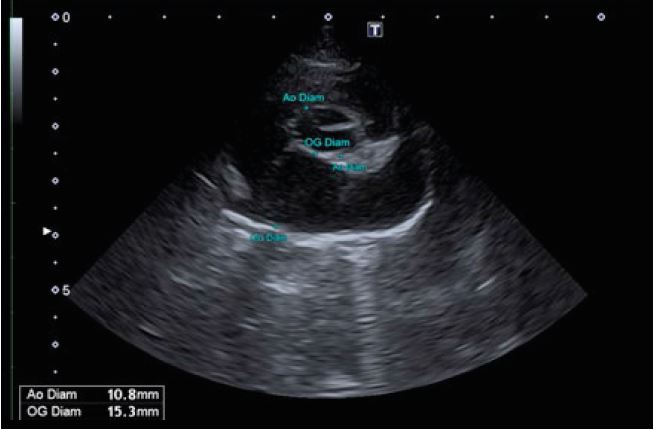

Обстеження серця в режимі 2D. Джерело: Клініка Альянс

Дослідження серця в 2D М-режимі з візуалізацією аорти та лівого передсердя. Джерело: Клініка Альянс.